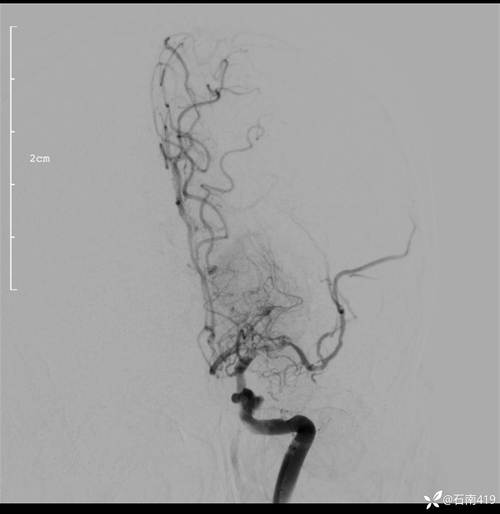

- 评估侧支循环: 这是CTA的另一个巨大优势,当主血管堵塞后,大脑会启动自身的“备用通道”(侧支循环)来代偿,CTA能清晰地显示这些侧支循环是否建立、是否良好。侧支循环越好,意味着缺血区域的脑组织能获得更多的“替代”血液,脑坏死的范围就越小,患者的神经功能缺损就越轻,预后也越好。

| DSA (数字减影血管造影) | “金标准”,空间分辨率最高,能动态显示血流;可同时进行血管内治疗(如取栓、支架植入)。 | 有创性检查,属于小型手术;有穿刺点出血、血管损伤、 stroke 等风险;检查费用高。 | 当CTA/MRA结果不明确时;或计划进行血管内介入治疗时。 |